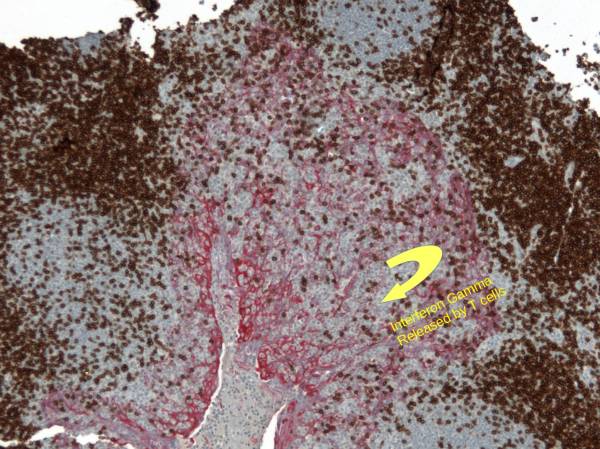

PDL1 Expression by Squamous Epithelium (Tonsil) protecting itself within a cryptitis

At low magnification (Left), one sees the heterogeneous expression of PDL1 in a tonsil which is used as a preferred positive on-slide control for PDL1. This expression is explained by a focal invasion of T cells reaching an infectious area (Center: DAB: CD3, RED: Cytokeratin). The T cells release Interferon-Gamma which stimulates local expression of PDL1 by the epithelium. The right picture shows PDL1 expression at higher magnification.